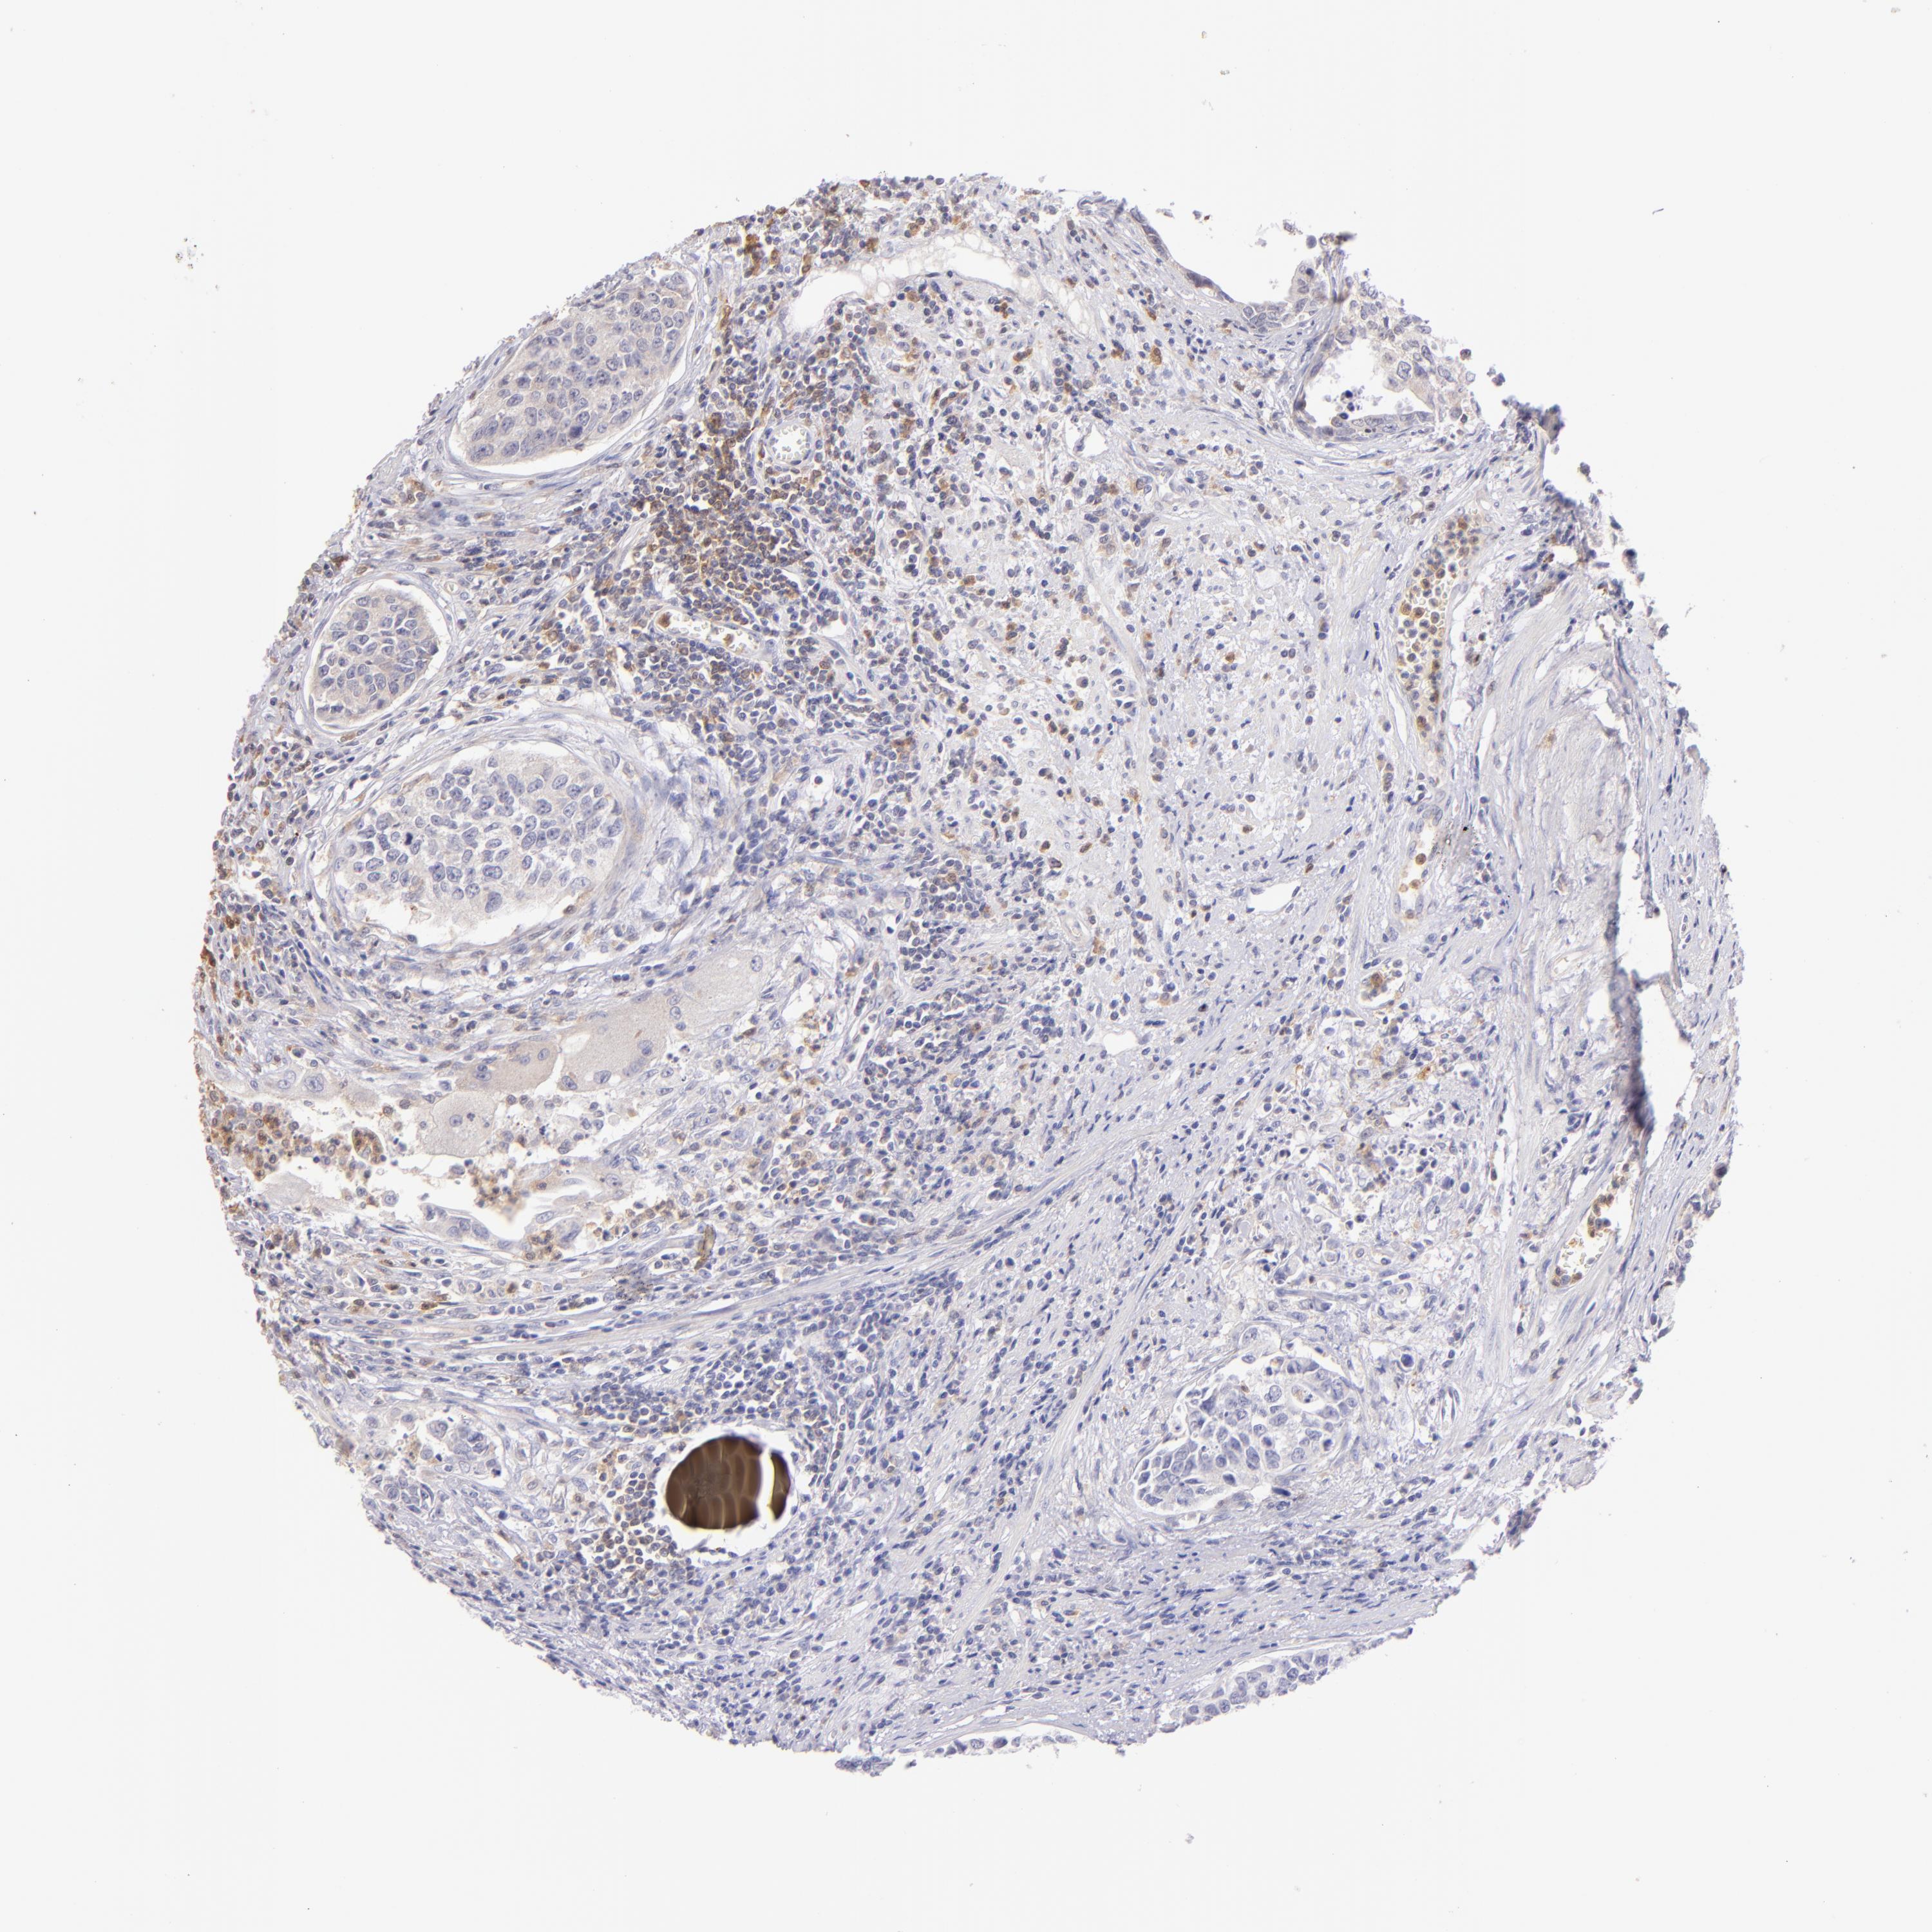

UROTHELIAL CANCER - Protein expressioni

A mouse-over function shows sample information and annotation data. Click on an image to view it in a full screen mode. Samples can be filtered based on level of antibody staining by selecting one or several of the following categories: high, medium, low and not detected. The assay and annotation is described here.

Note that samples used for immunohistochemistry by the Human Protein Atlas do not correspond to samples in the TCGA dataset.

Antibody stainingi

Antibody staining in the annotated cell types in the current human tissue is reported as not detected, low, medium, or high, based on conventional immunohistochemistry profiling in selected tissues. This score is based on the combination of the staining intensity and fraction of stained cells.

Each image is clickable and will lead to virtual microscopy that enables deeper exploration of all samples and also displays staining intensity scores, fraction scores and subcellular localization as well as patient and tissue information for each sample.

Antibody HPA001198

Antibody HPA002028

Antibody CAB016689

Antibody CAB080300

Staining

High

Medium

Low

Not detected

Intensity

Strong

Moderate

Weak

Negative

Quantity

>75%

75%-25%

<25%

None

Location

Nuclear

Cytoplasmic/membranous

Cytoplasmic/membranous,nuclear

Urothelial carcinoma, High grade

Urothelial carcinoma, Low grade

Adenocarcinoma, NOS